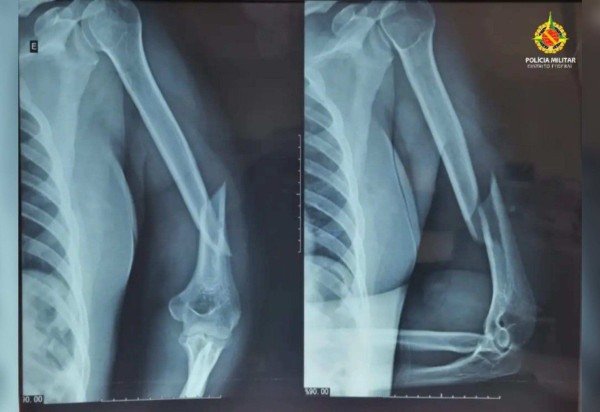

Ao chegarem ao local, os policiais encontraram a vítima com hematomas no rosto, inchaço nos olhos, sangramento nos ouvidos, fratura no úmero e luxação no ombro esquerdo. Segundo o Serviço de Atendimento Móvel de Urgência (Samu), o quadro clínico é compatível com trauma cranioencefálico (TCE).